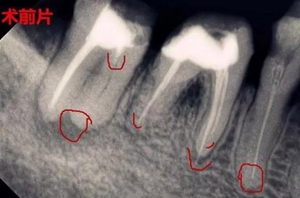

3.jpg

所以根管治療清理干凈殘髓至關(guān)重要,還有牙膠尖一定要完整填充根管,不能出半點差錯,否則牙齦上的膿包會越變越大,及時排膿消炎減少瘺管感染,牙齦也可以慢慢恢復(fù)正常